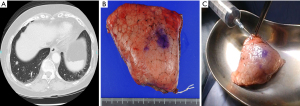

The resected specimens were inflated by the careful instillation of air. Puncture was performed at a distant site, where the pulmonary lesion was absent, using a 23-G puncture needle connected to an appropriately sized syringe. The instillation was done slowly in order to prevent alveolar wall destruction. The degree of inflation differs among specimens because air leak from the puncture site or stapled site eventually develops. After the specimen was placed in a plastic container, the specimen along with the container underwent conventional 64-detector CT (Revolution GSI; GE, Chicago, IL, USA) as soon as possible. The scan parameters were as follows: tube voltage, 80 kV; rotation time, 0.6 s; beam width, 20 mm; pitch, 1.375; slice thickness, 0.625 mm; slice interval, 0.625 mm; scan field of view (FOV), 8 cm; matrix, 512×512; recon type, HD Lung; noise index, 10. It generally takes 5 minutes or less for scanning of the resected specimen and image acquisition. The obtained images were evaluated intraoperatively in the operating room on multi-planner reconstruction images. Figures 1-3 show two representative cases with primary lung cancer.

One of the most important benefits of the present method is that we can measure the distance between the intrapulmonary lesions and any staple line (Figure 2) on multiplanar reconstruction images. This means that we can create multiple section images of the resected specimens without cutting the specimen itself, which can aid in determining how to make additional cut lines during performing additional resection for insufficient surgical margin.